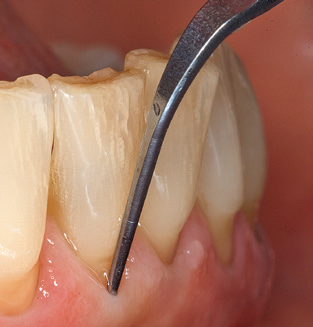

L'aggiornamento della storia medica del paziente è un aspetto importante di SPT e dovrebbe avvenire almeno una volta all'anno. Aiuta il team dentale a identificare e documentare eventuali nuovi fattori di rischio. Soprattutto quando un paziente viene curato per molti anni, è importante stabilire se i fattori di rischio per la salute specifici del paziente e generali sono cambiati. Ciò riguarda principalmente un aumento del rischio a causa del diabete, ma altre condizioni generali (malattie cardiovascolari e neoplasia) possono anche produrre un profilo di rischio modificato a seguito del trattamento eseguito e della somministrazione dei farmaci. Di conseguenza, l'aggiornamento della storia medica come parte di SPT è molto importante, poiché un profilo di rischio modificato può innescare la necessità di adattare l'intervallo di trattamento. Nel passaggio successivo, è importante prestare la dovuta attenzione alla diagnostica. Mentre gli strumenti sono un aspetto centrale di SPT, i risultati e la loro documentazione non devono mai essere trascurati. I risultati parodontologici sono essenziali per una buona diagnosi; aumenti della profondità della tasca e l'indice BOP sono chiari indicatori dell'avanzamento della malattia parodontale e perimplantare. Pertanto, il team non dovrebbe evitare di sondare anche gli impianti, con l'obiettivo di raccogliere i dati richiesti. Allo stesso tempo, è importante utilizzare sonde parodontali con segni millimetrici. Le sonde metalliche sono già state utilizzate per determinare la profondità della tasca attorno ai denti naturali per decenni. Nel caso degli impianti, la sfida di registrare profondità delle tasche corrette e riproducibili è ancora maggiore. Poiché la discrepanza tra il diametro dell'impianto e il contorno della sovrastruttura si traduce regolarmente in un over-contouring della sovrastruttura, le sonde flessibili che presentano ancora marcature millimetriche sono una soluzione sensata per misurare la profondità della tasca attorno agli impianti (ad es. Colorvue Kit PCV11KIT6, HuFriedy; Fig. 4 ).

Fig. 4: Sonde flessibili con marcature millimetriche sono consigliate per il sondaggio di impianti dentali (ad es. Colorvue Kit PCV11KIT6, HuFriedy). - Fig. 5a e b: Un inserto diritto (1P, W&H Dentalwerk Bürmoos GmbH) è uno strumento adatto per l'uso su tutti i denti naturali. - Fig. 6: Inserti curvi (3Pr / 3Pl, W&H Dentalwerk Bürmoos GmbH) si prestano alla lavorazione di aree difficili da raggiungere del dente e delle superfici radicolari (ad es. Forcazioni). - Fig. 7: L'inserto esagonale conico per la pulizia dell'impianto (1I, W&H Dentalwerk Bürmoos GmbH) consente una pulizia atraumatica ed efficace della superficie della corona e del moncone. - Fig. 8: Le curette in titanio e carbonio sono strumenti adatti per la pulizia manuale delle superfici dell'impianto.